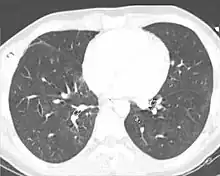

X-ray

Chest X-ray is the most common method used for diagnosis,[37] and may be used to confirm a diagnosis already made using clinical signs.[20] Consolidated areas appear white on an X-ray film.[42] Contusion is not typically restricted by the anatomical boundaries of the lobes or segments of the lung.[27][43][44] The X-ray appearance of pulmonary contusion is similar to that of aspiration,[32] and the presence of hemothorax or pneumothorax may obscure the contusion on a radiograph.[25] Signs of contusion that progress after 48 hours post-injury are likely to be actually due to aspiration, pneumonia, or ARDS.[10]

Although chest radiography is an important part of the diagnosis, it is often not sensitive enough to detect the condition early after the injury.[35] In a third of cases, pulmonary contusion is not visible on the first chest radiograph performed.[7] It takes an average of six hours for the characteristic white regions to show up on a chest X-ray, and the contusion may not become apparent for 48 hours.[7][27][43] When a pulmonary contusion is apparent in an X-ray, it suggests that the trauma to the chest was severe and that a CT scan might reveal other injuries that were missed with X-ray.[2]